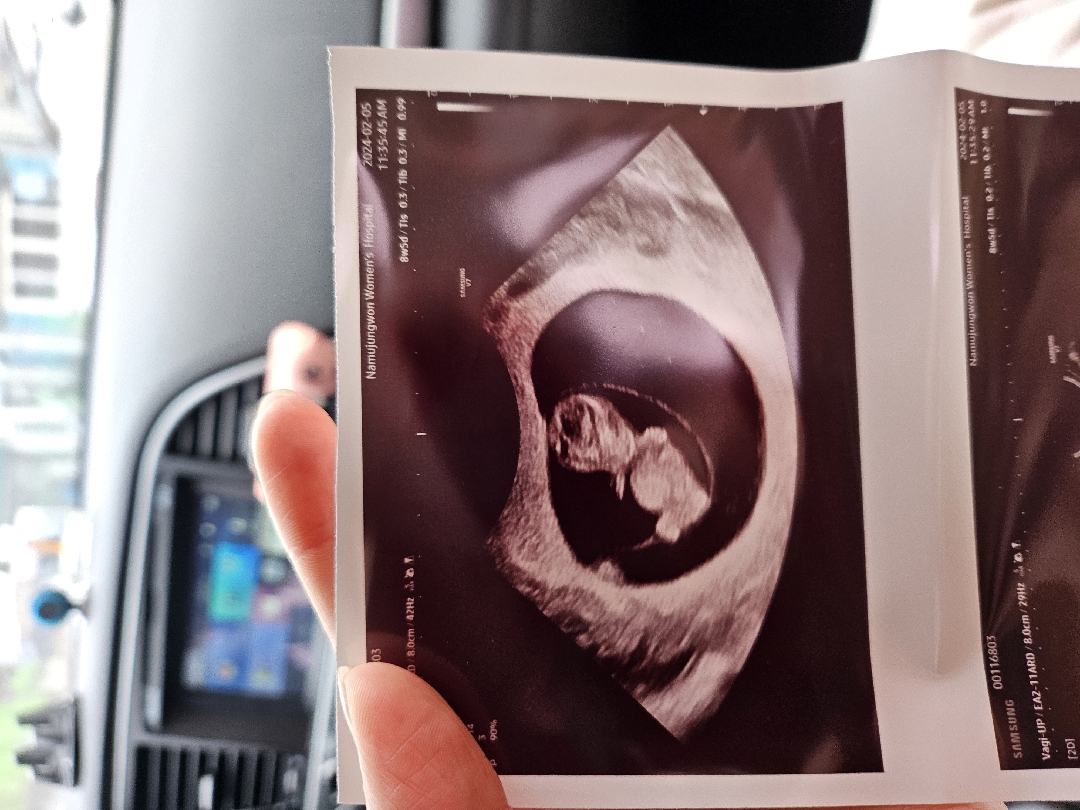

8주5일 초음파사진

다른초음파사진은 이렇게 배가 안나왔는데 왜 저희 애기는 배가 나왔을까요ㅋㅋ 너무귀엽긴한데 다른 초음파사진이랑 달라서 걱정도되구,, 다들 어떠세요?